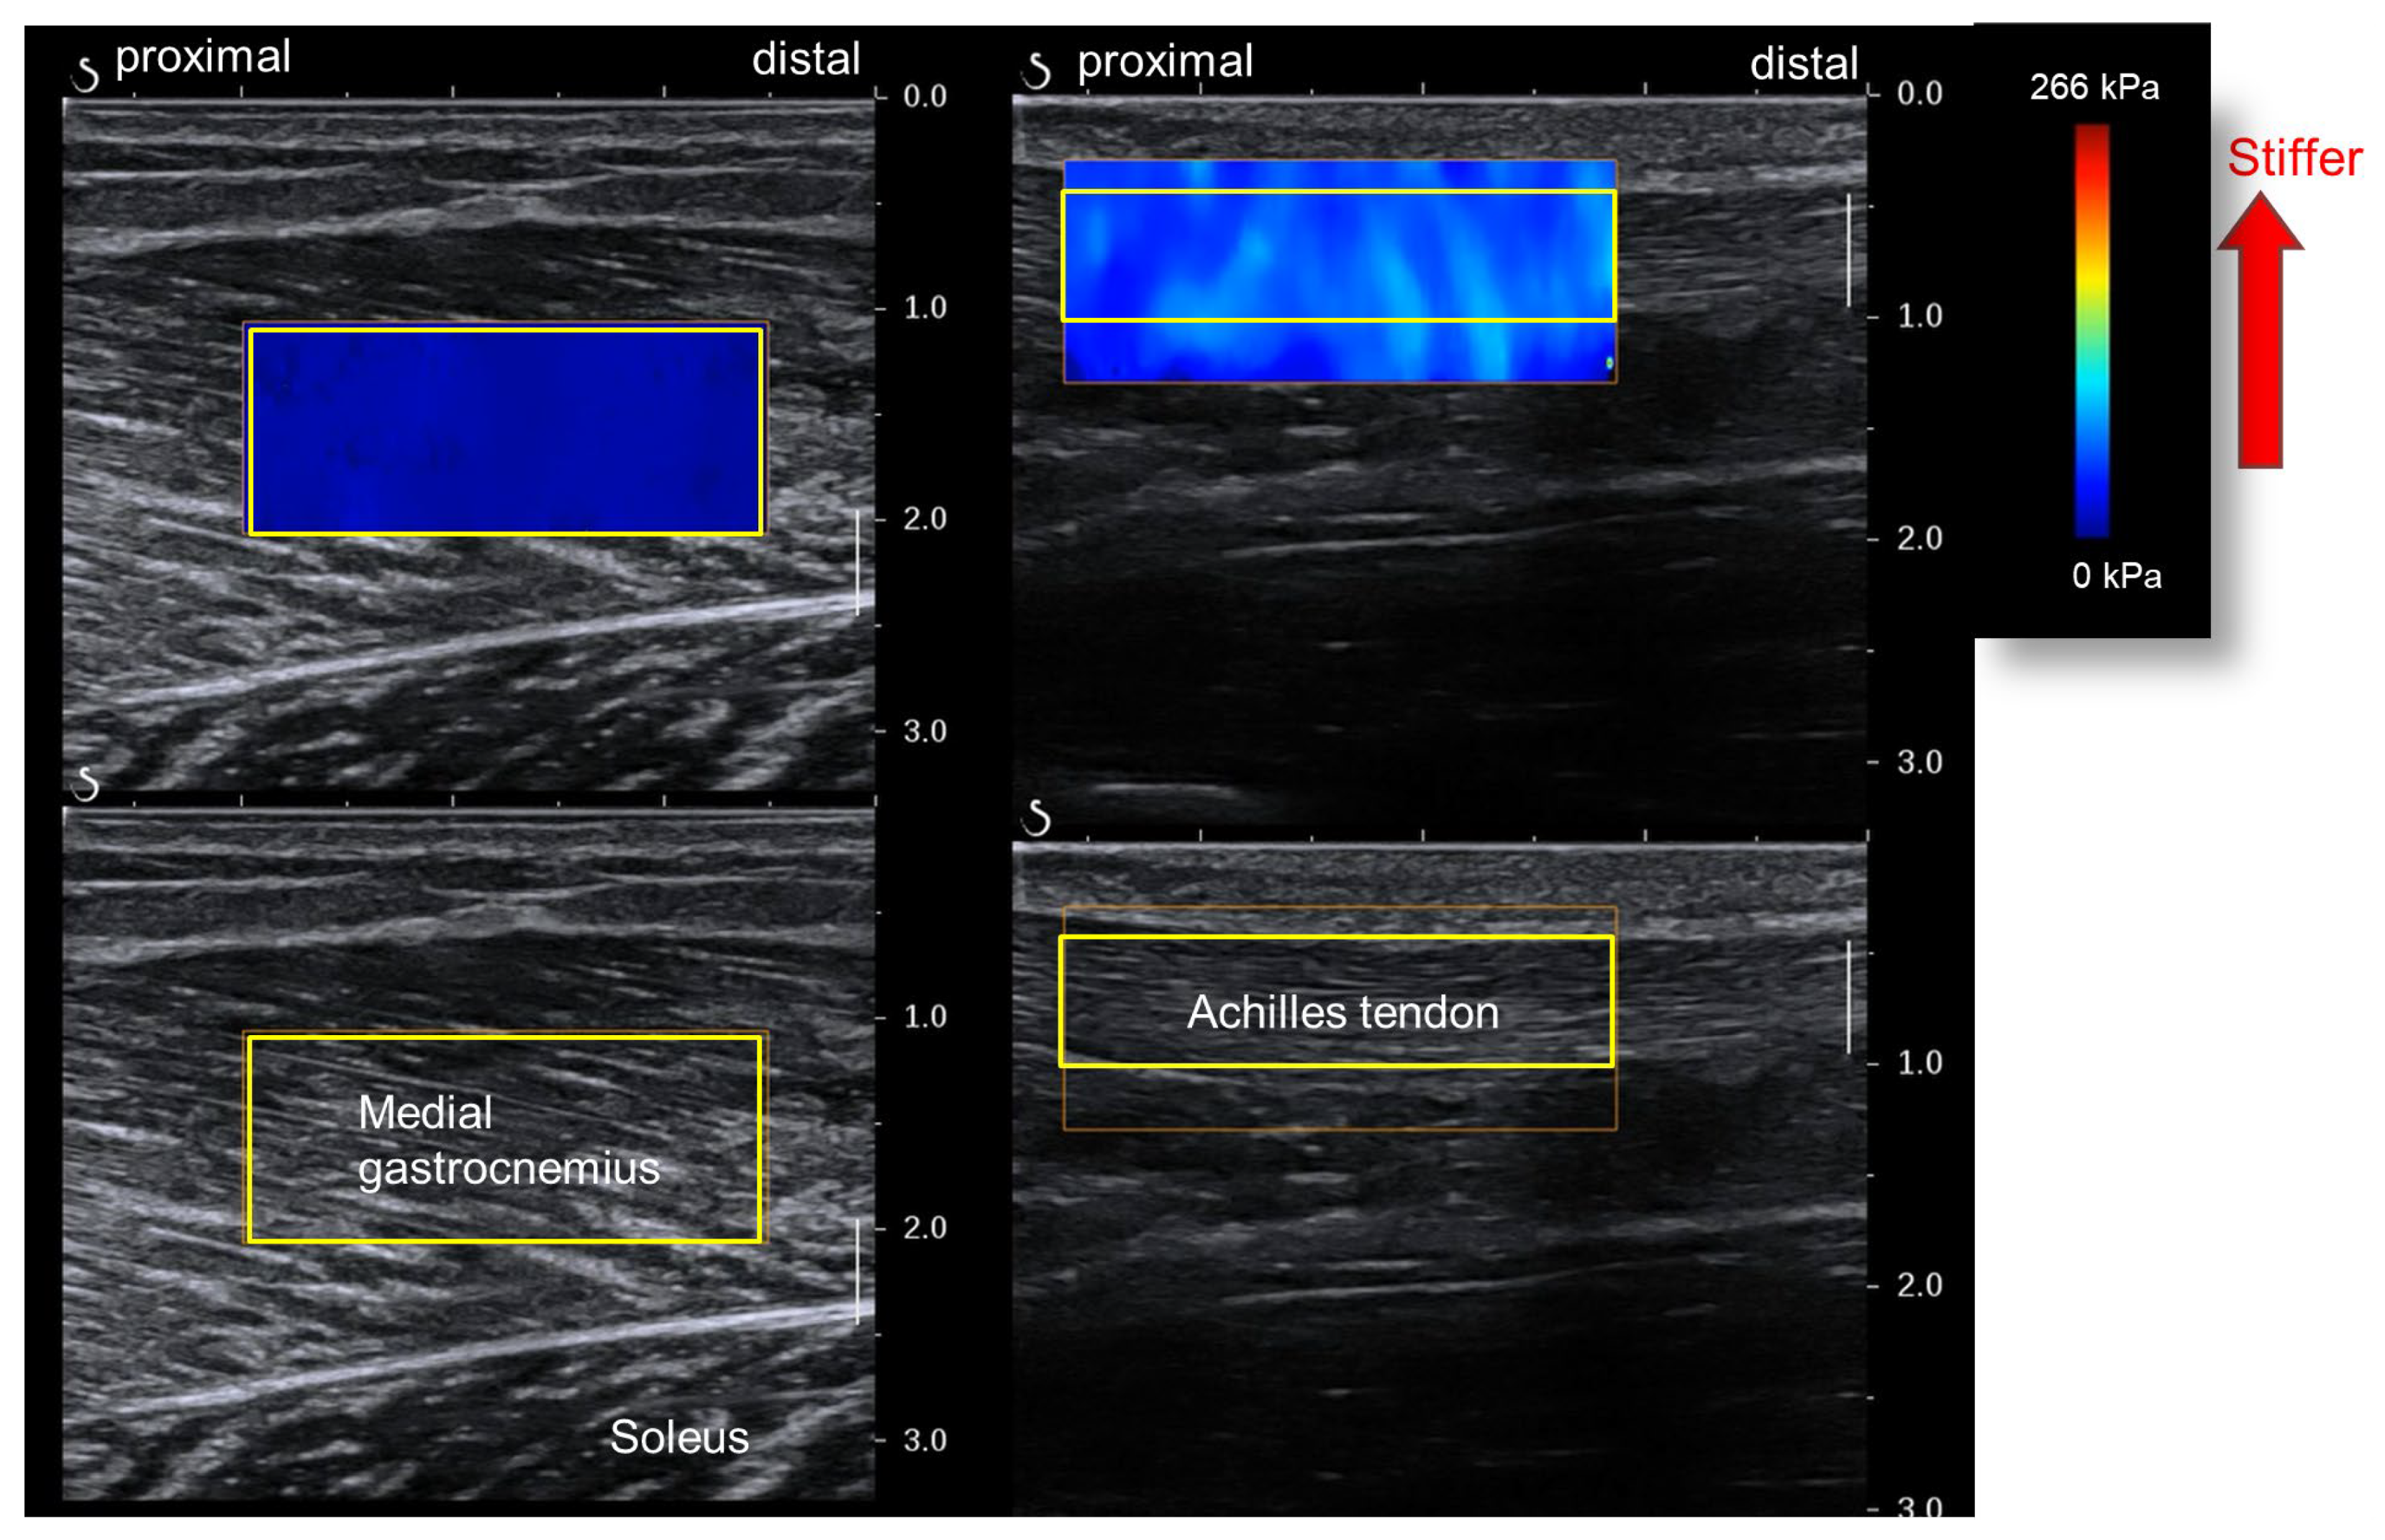

We used an elastography image analysis program (T.K.K. 5840, Takei Scientific Instruments, Niigata, Japan) to analyze the ultrasound images on a personal computer (Figure 4). We set a rectangular region of interest (ROI) for each image and obtained the mean value of the shear modulus within the ROI. The MG stiffness for each joint angle was defined as the mean of three out of the five shear modulus values obtained from the five ultrasound images, excluding the largest and smallest.

Figure 4.

Analysis of muscle and Achilles tendon shear moduli wave velocities (yellow squares—regions of interest [ROIs]). The muscle shear modulus is obtained from the medial gastrocnemius (left). The Achilles tendon shear modulus is obtained from the free tendon part (right).

The ankle joint angle for the AT shear modulus measurement was 20° plantar flexion. The participants’ posture for the measurements was the same as that for MG stiffness, except for the joint angle. Based on previous research, the AT measurement site was the free part of the tendon distal to the distal end of the SOL’s belly [16]. Ultrasound images were acquired and analyzed similarly to those for the MG to determine AT stiffness for each joint angle (Figure 4).